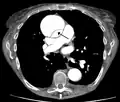

Computed tomography angiography is a fast, noninvasive test that gives an accurate three-dimensional view of the aorta. These images are produced by taking rapid, thin-cut slices of the chest and abdomen, and combining them in the computer to create cross-sectional slices. To delineate the aorta to the accuracy necessary to make the proper diagnosis, an iodinated contrast material is injected into a peripheral vein. Contrast is injected and the scan performed using a bolus tracking method. This type of scan is timed to an injection to capture the contrast as it enters the aorta. The scan then follows the contrast as it flows through the vessel. It has a sensitivity of 96 to 100% and a specificity of 96 to 100%. Disadvantages include the need for iodinated contrast material and the inability to diagnose the site of the intimal tear.

CT with contrast demonstrating aneurysmal dilation and a dissection of the ascending aorta (type A Stanford)

Chest CT with descending (type B Stanford) aortic dissection (red circle)

Type A dissection with pericardial effusion as a result.